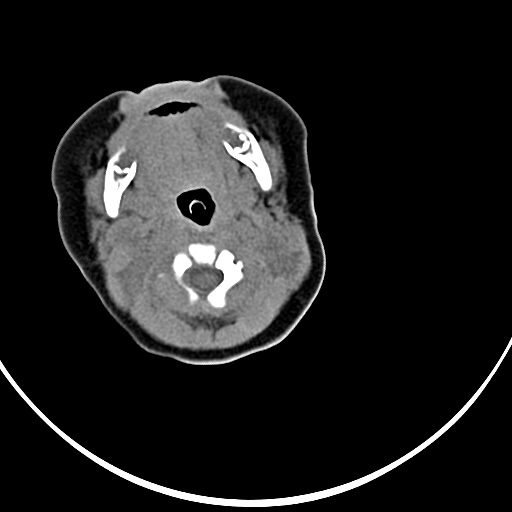

患者,男,1月,出生后一月,无明显诱因出现颈部左前方肿块。体检:左侧颈部轻度凸起包块,触之较硬。

患者,男,1月,左经部轻度凸起包块,质硬。

病灶与左侧胸锁乳突肌分界不清,软组织密度,不似囊性改变,从病人的年龄及病变性状首先要除外先天性斜颈(肌性斜颈)可能。

左侧胸锁乳突肌肿大,考虑产伤所致

胸锁乳突肌挛缩(斜颈)?